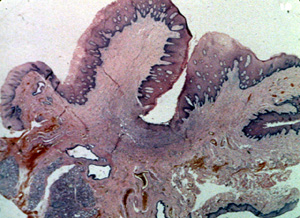

| El

tratamiento para el épulis fisurado normalmente es la biopsia por escisión . En la mayoría de los casos, el encogimiento ocurrirá si

las dentaduras postizas no están estropeadas; sin embargo, porque la

lesión está compuesta por tejido fibroso muy denso, la resolución

completa generalmente no ocurre. Este espécimen indica el tipo de

terapia empleado. El patólogo realizará las secciones múltiples a

través del espécimen para evaluar todas las porciones.

Esta

microfotografía de baja resolución

ilustra bien el aspecto lobulado de la lesión. Hay una

invaginación profunda en la porción central en que la pestaña de la

dentadura postiza fue localizada. |